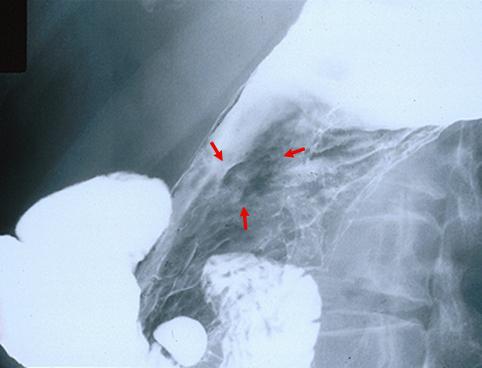

질환(병리주체)의 분류 악성 상피성종양/선암

부위(장기별) 위(부위)/체부

검사방법 X-P

종양의 육안분류 0형(표재형)/IIc형(IIc)

종양의 최대경(밀리미터) 15~19

종양의 심달도 sm